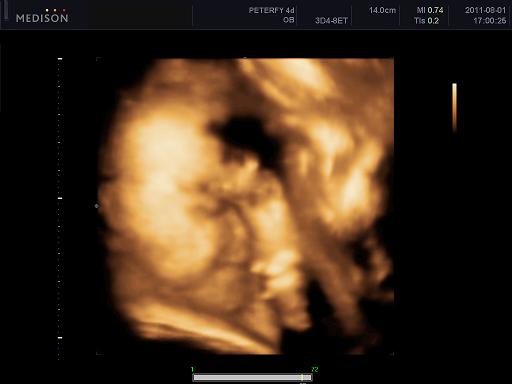

Velünk minden oké szerencsére, dundisodok én is, a baba is tök szuperül van ééééés tegnap voltunk végre 4D-n, annyira nagy élmény volt lányok!!!! Nem is gondoltam h ez ennyire jó dolgo, azzal együtt, hogy Alma nagyon bújócskázott, végig az arcát simizte meg takargatta, csak néha kaptunk egy kis mosolyt de imádom, végtelenül nagy boldogság ez a kis csöppség!!!!! :)

1250 grammos és kis ficánka, meg a szonográfus csaj is mondta hogy mennyire kis cserfes már most! :D

Kép